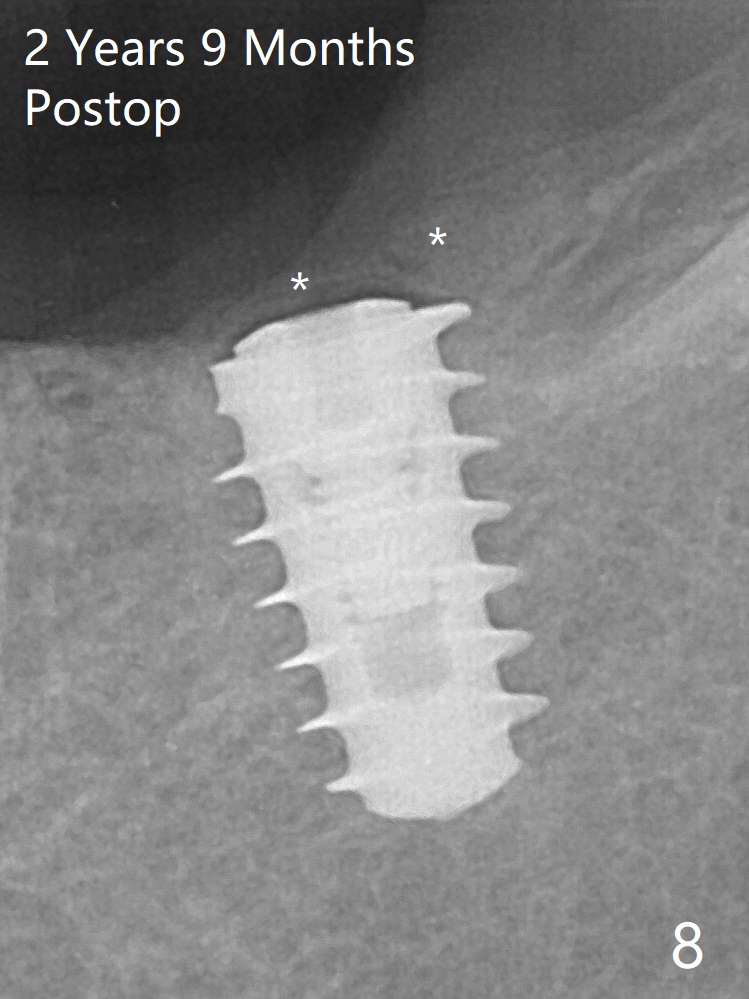

In fact, the mesial crest of the socket could be used as a more secure landmark (bony vs. soft tissue) for osteotomy depth (Fig.4 arrowhead) with drill stopper. To place the implant subcrestal, the initial osteotomy should be 1-2 mm deeper. When she returns 2 years 9 months postop, the wound has healed. The implant needs to be uncovered. Make sure to have clearance for a healing abutment. Use sensor 1 for PAs before and after uncover. The implant appears to be tilted distal. An angled abutment may be required. Take PA for seating confirmation. Guided surgery is preferable. The implant plateau is covered by the bone 2 years 9 months postop (Fig.8 *). The healing screw is removed with difficulty, while a 6x3 mm healing abutment is placed with resistance, probably related to interference from the distal crest (Fig.9 *). It is much easier with removal of the crest bone using surgical bur, because of clearance (Fig.10 *). It is the best to have a particular drill to remove the excess bone. There is no interference to insert and torque a 5x4(2) mm pair abutment 2 weeks post uncover (Fig.11). Due to poor trajectory (guide necessity) and tight proximal contact, the crown is not completely seated (Fig.12). However, the abutment screw is unlikely to get loose in the future.